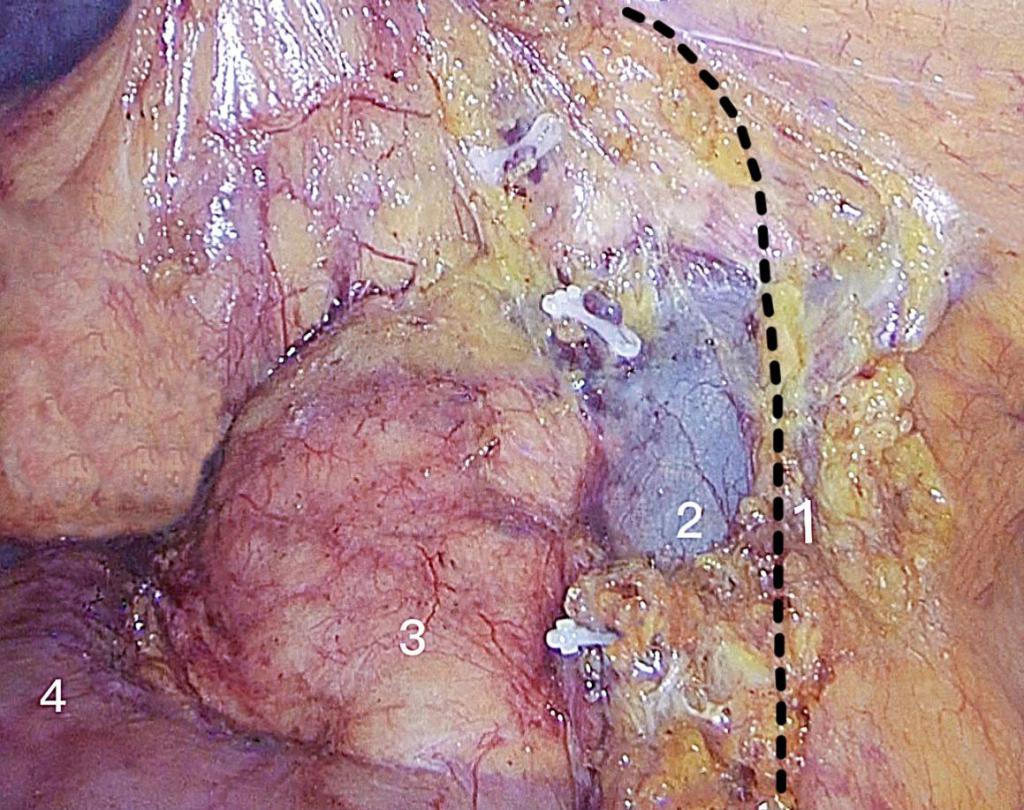

周乐其,冯波,苏浩,等. 以肠系膜上动脉左侧为右半结肠癌D3根治术淋巴结清扫内侧界可行性研究[J]. 中国实用外科杂志,2019,39(07):712-715.

陈垚,蔡丙华,朱建伟,等. 右半结肠癌根治术中全结肠系膜切除的内侧界限选择[J]. 实用临床医药杂志,2021,25(2):84-86.

ZHOU L, DIAO D, YE K, et al. The Medial Border of Laparoscopic D3 Lymphadenectomy for Right Colon Cancer: Results from an Exploratory Pilot Study[J]. Dis Colon Rectum, 2021,64(10):1286-1296. doi:10.1097/dcr.0000000000002046